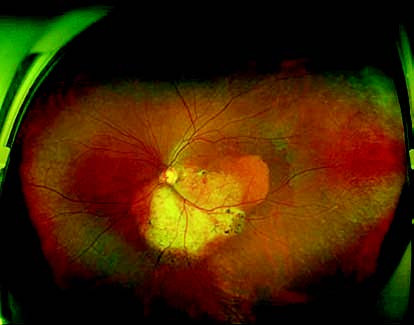

Figure 1 Wide-field fundus photograph of the left eye with choroidal osteoma

An oval yellow-white lesion is observed inferior to the optic disc in the temporal region, with well-defined margins measuring approximately 5 disc diameters (DD). The surface of the lesion contains neovascularization and scattered pigment deposits, with surrounding depigmentation of the retinal pigment epithelium.